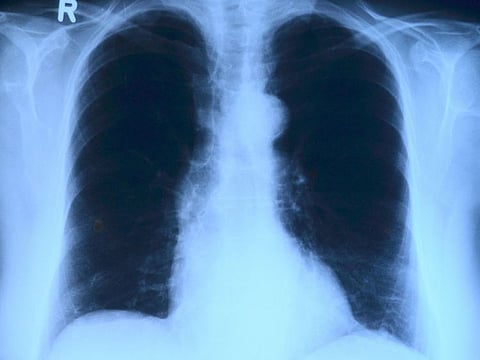

Study suggested that the fatty tissue alters the structure of people's airways

Canberra: Researchers have found that fatty tissues accumulate in the airway walls, particularly in people who are overweight or obese.

The study, published in the European Respiratory Journal, suggested that the fatty tissue alters the structure of people's airways and this could be one reason behind the increased risk of asthma.

The study showed that fatty tissue accumulates in the walls of the airways. The analysis revealed that the amount of fat present increases in line with increasing BMI.

"We've found that excess fat accumulates in the airway walls where it takes up space and seems to increase inflammation within the lungs," said the study's co-author Peter Noble.

"We think this is causing a thickening of the airways that limits the flow of air in and out of the lungs, and that could at least partly explain an increase in asthma symptoms," Noble said.